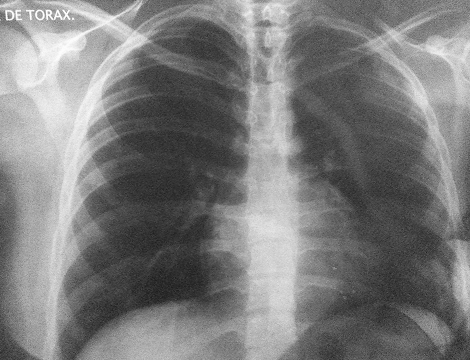

Paciente Esthefany Medina

Paciente diagnosticada con hipertrofia cardíaca (cardiomegalia), una condición caracterizada por el agrandamiento del corazón debido al engrosamiento de sus paredes musculares o la dilatación de sus cavidades.

A través del tratamiento, se buscó regular el flujo de energía y calmar el fuego interno, ayudando al corazón a recuperar su equilibrio funcional y emocional.

Evolución del corazón inflamado